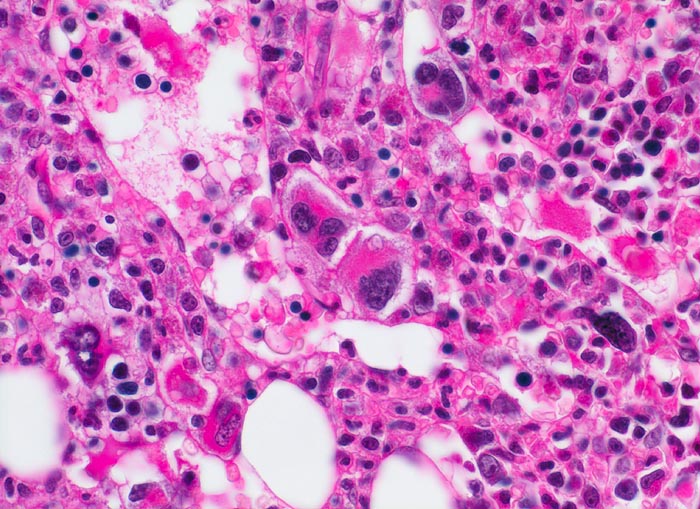

Die Erkrankung ist charakterisiert durch Knochenmarkfibrose, Hepato-Splenomegalie und extramedulläre Blutbildung. Diese findet sich am häufigsten in Leber und Milz, seltener in Lymphknoten, Nieren, Nebennieren, Dura mater, Gastrointestinaltrakt, Lunge, Mamma oder Haut. Blut und Knochenmark sind immer involviert. Die Krankheit entwickelt sich über ein initiales präfibrotisches Stadium mit hyperzellulärem Knochenmark zum fibrotischem Stadium (vorliegendes Präparat). Das fibrotische Stadium ist gekennzeichnet durch eine Vermehrung von Reticulin- und/oder Kollagenfasern und oft einer Knochenneubildung (=Osteomyelosklerose). Die Zellularität des Knochenmarks ist dann vermindert und dilatierte Marksinus enthalten intraluminale Blutbildungsherde. Es besteht eine auffallende Proliferation von Gruppen bildenden atypischen Megakaryozyten.

• Vermehrung von atypischen, in Gruppen liegenden Megakaryozyten mit abnorm lobulierten Kernen.

• Nacktkernige (zytoplasmaarme) und vergrösserte Megakaryozyten.

• Hyperplastische ausreifende Myelopoese.

• Hypoplastische Erythropoese.